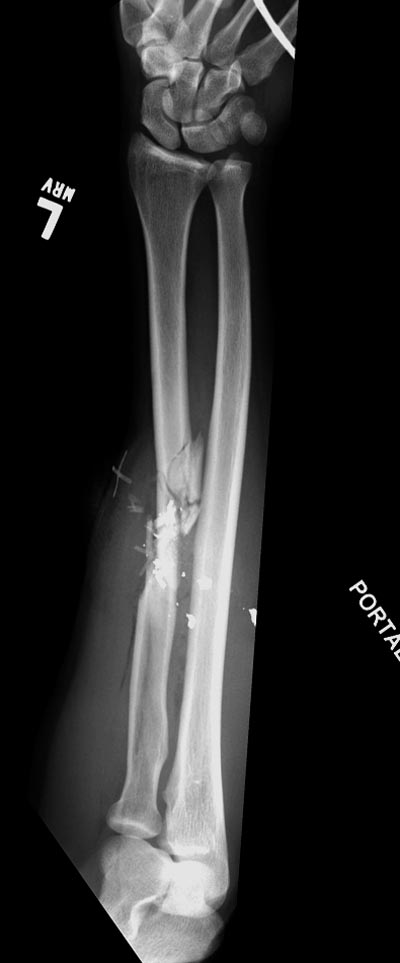

Здесь примеры: двоюродные братья с ранением предплечья, у одного

локтевая, а у второго лучевая. В следующее утро локтевая фиксирована без

обнажения фокуса травмы из небольших доступов, а второй из обычного

волярного доступа. А клинический снимок из прошлых операций...

Вложение не в текстовом формате было извлечено…

Имя     : GSW radius CRM 4.jpg

Тип     : image/jpeg

Размер  : 32161 байтов

Url     : http://weborto.net:8080/pipermail/ortho/attachments/20140728/123f732a/attachment-0013.jpg